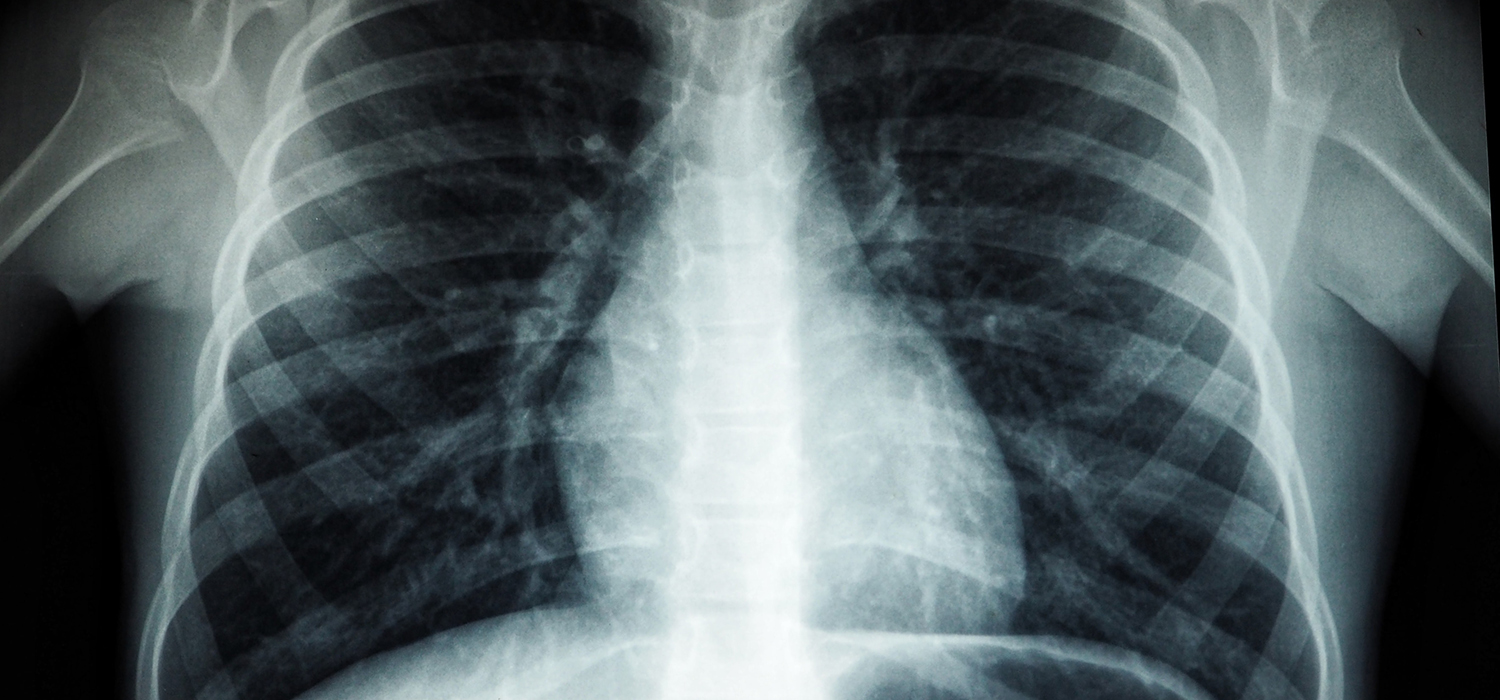

It is important to designate all areas and give examples of the unique and personalised information medical imaging technology provides. Imaging is the first step from clinical symptoms to diagnosis in many diseases. Imaging has played this role for decades. It assesses the location and extent of disease in individual patients, identifies structural abnormalities and physiological milieu, and provides critical information for selecting appropriate treatment.

Early and accurate assessment of treatment response is important in PM as it can influence decisions regarding treatment discontinuation, modification, and additional treatment. Imaging can detect treatment response early, so patients can avoid long-term exposure to ineffective treatments and use alternative therapies early. In addition, medical imaging helps physicians plan and manage individual surgical or minimally invasive treatments.